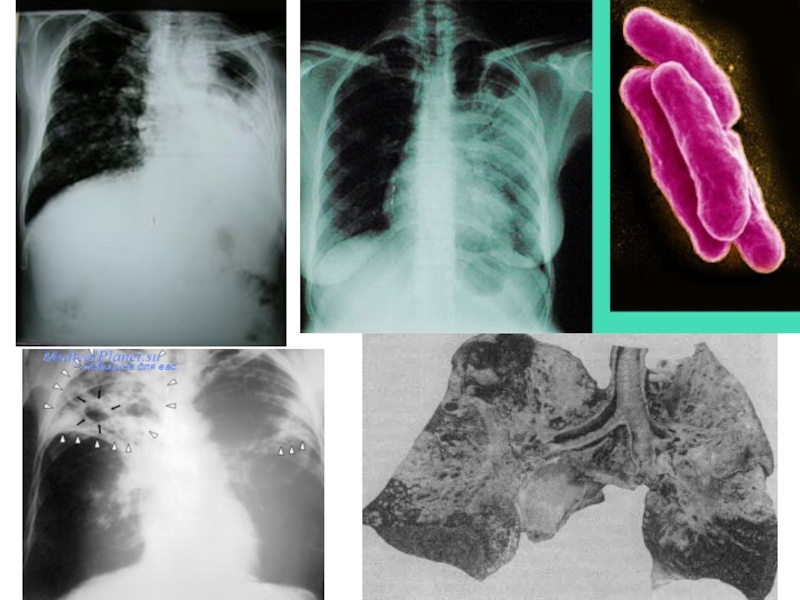

Слайд 3ТУБЕРКУЛЕЗ ҚОЗДЫРҒЫШТАРЫ

Туберкулез (tuberculosis; латынның tuberculum - төмпешік) –

микобактериялар туғызатын жұқпалы созылмалы ауру, әр түрлі мүшелер мен жүйелерді

(өкпе, асқорыту жолдары, тері, сүйек, зәр шығару ж/е т.б.) зақымдаумен сипатталады. Туберкулез қоздырғышын (1882 ж) Роберт Кох ашқан, клиникасын Гиппократ сипаттаған.

Патогенді микобактериялардың 3 түрлі белгілі:

M. tuberculosis (адамдық түрі – адамдарда 92% жағдайда туберкулез тудырады);

M. bovis (өгіздік түрі – 5% жағдайда);

M. africanum н/се avium (құстық түрі - 3% жағдайда). Бұлардың 3 де морфологиялық, дақылдық, биохимиялық ж/е патогенді құрылымымен ерекшеленеді.

Слайд 6МОРФОЛОГИЯСЫ Ж/Е ТИНКТОРИАЛДЫҚ ҚАСИЕТТЕРІ.

M. tuberculosis - ұзын, жіңішке,

аздап иілген таяқшалар. Тек адам үшін патогенді. Сезімтал биологиялық үлгі

– теңіз шошқасы.

M. bovis – қысқа, жуан дәнді таяқшалар. Сезімтал биологиялық үлгі – қояндар мен теңіз шошқасы. Ірі-қара мал үшін патогенді.

M. africanum – жұқа, ұзын, жіпше тәрізді таяқшалар. Сезімтал биологиялық үлгі – қояндар. Адам мен құстар үшін патогенді.

Барлық микобактериялар бояуларды нашар қабылдайды. Циль-Нильсен әдісімен қызыл түске боялады, грам оң, қозғалмайды, спора ж/е капсула түзбейтін, талшықтары жоқ таяқшалар.

Слайд 22ТУБЕРКУЛЕЗ ПАТОГЕНЕЗІ

ТУБЕРКУЛЕЗ ПАТОГЕНЕЗІ

Слайд 23ТУБЕРКУЛЕЗ ПАТОГЕНЕЗІ

Бронхогенді, лимфогенді және гематогенді микобактериялардың диссеминациясы біріншілік туберкулез ошағында

жүруі мүмкін және олар басқа мүшелер мен тіндерден өтуі мүмкін.